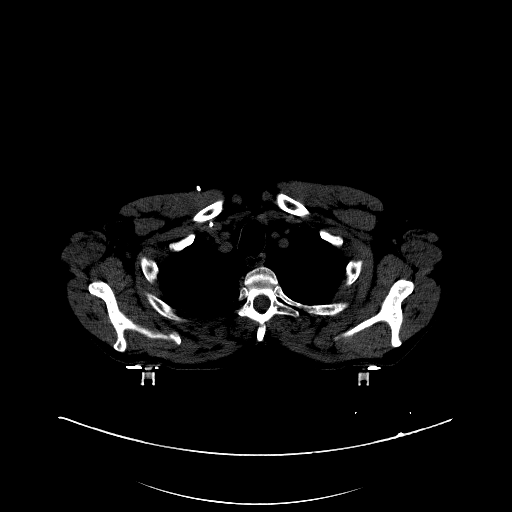

The cognition of artificial intelligence is important for computer-aided diagnostic. Multi-organ segmentation can help the machine understand the structure of the human body, which is very important for all the relevant tasks. Therefore, some research has focused on single- or multi-organ segmentation tasks, such as the liver([79, 80]) and the pancreas([81, 82]). In this case study, we use a VNet-based neural network to solve the multi-organ segmentation challenge, SegTHOR, [83]. The SegTHOR challenge includes about 40 CT images of the chest, and aims at the segmentation tasks of the heart, aorta, trachea, esophagus, and further more.

As Fig. 11 shows, The workflow of this case study includes six parts: “input”, “pre-processing”, “dataset management”, “neural network”, “visualization”, and “analysis”. The “input” includes images of the chest and annotations.

“Pre-processing” rescales the range of the image values with a window width and a window level. Then, the input images are re-sampled with the “resample” tool to change their size. The “dataset management” function subsequently splits the dataset into a training and a testing set randomly, yet reproducibly.

“Neural network” employs VNet to train and validate the model, which can be used to segment organs from the chest. Then, the segmented images can be visualized via the “organ visualization” option, and the results can be analyzed with the “result analysis” tool to generate an MS-Excel based report.

VI-3 Result and Visualization